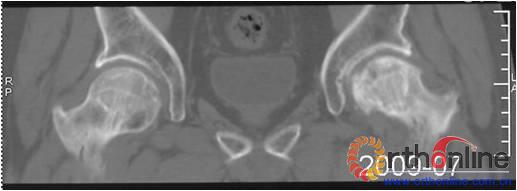

(三) 国内外的研究显示,在对股骨头坏死塌陷预测的方法中,以日本骨坏死研究会(Japanese investigation committee,JIC)依坏死部位对ONFH分型的准确性较高(图4)。本分型对JIC分型法进行改良,并对比。

图 4 日本骨坏死研究会依坏死部位分型

Fig 4 Japanese investigation committee (JIC) classification for ONFH